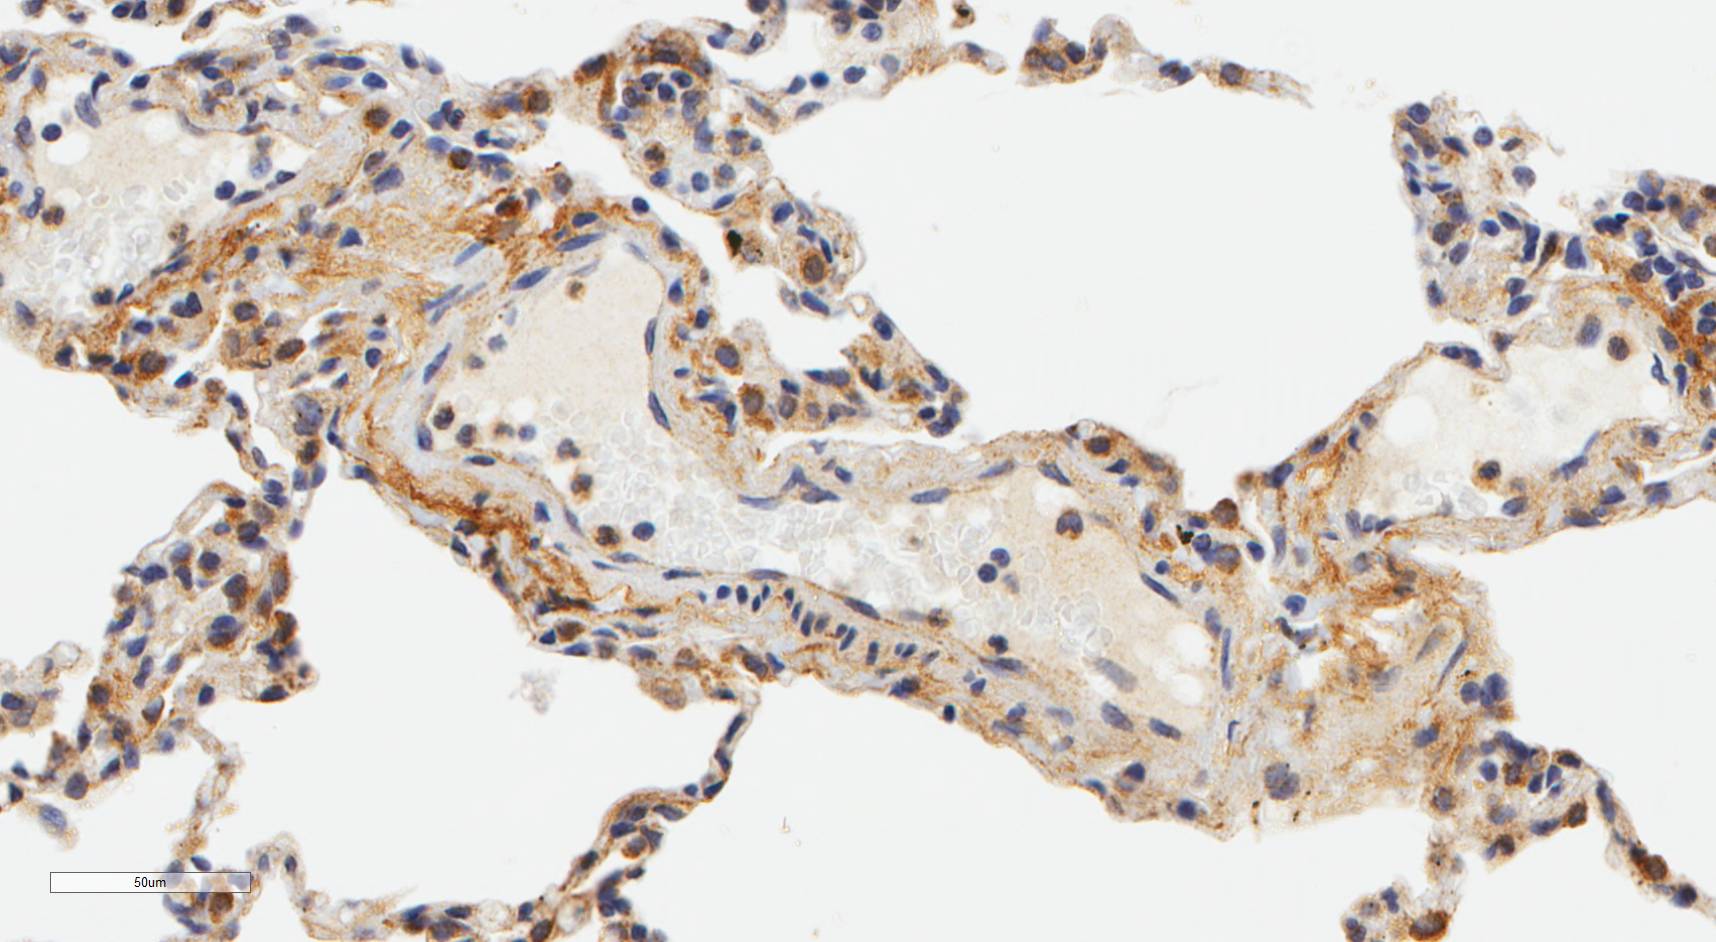

Laminin N terminus alpha31 (LaNt a31) is a really interesting laminin-related protein that the Hamill lab has been investigating for a while. Until recently, our studies focused entirely on the epithelial tissues of the skin, the surface of the eye and oral squamous cell carcinoma. However, we’ve always known that this relatively unstudied protein is also expressed by other tissues. As a first (and really important) step to understanding what this protein’s role is in tissue function, we used our new mouse monoclonal antibodies against the human form of LaNt a31 to screen a wide-range of human tissues.

Below you can see some of our favourite images from the selection. Click on an image to view as a slideshow.

You can see the whole story in the paper by Lee Troughton et al., available here.